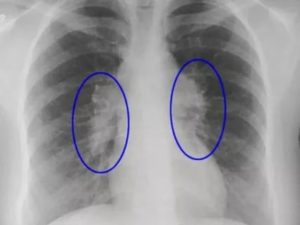

Поражение легких коронавирусом на рентгеновских снимках

Это нарушает вентиляцию, что проявляется клинически одышкой, а на рентгенограмме или томограмме определяются очаги затемнения (симптом «матового стекла»).

При прогрессировании болезни очаговые изменения сливаются между собой и занимают все большую площадь легочной ткани (симптом «белого легкого»). Это существенно ухудшает дыхание, вплоть до необходимости подключения больного к аппарату искусственной вентиляции легких. Между дольками уплотняются прослойки (перегородки) соединительной ткани (симптом «булыжной мостовой»).